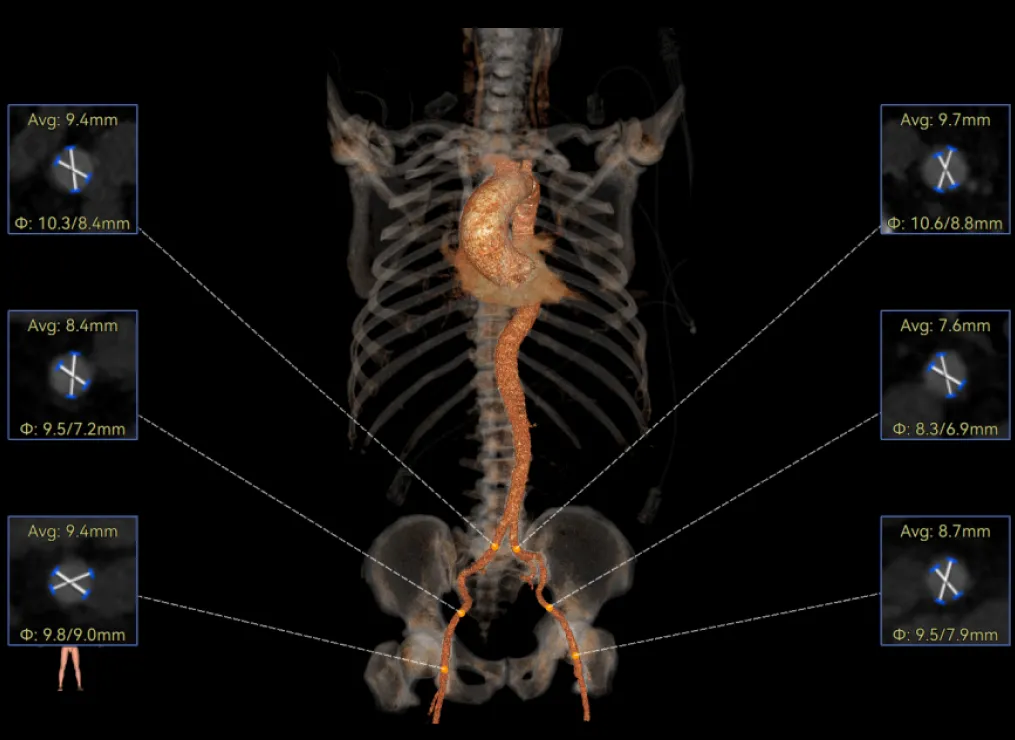

患者病史 男性,74y, 因 “发现心脏瓣膜病 1 年,加重伴喘气半年” 入院。门诊检查显示主动脉瓣重度AS并伴轻-中度AR。患者基础疾病较多:胸腹主动脉多发穿透性溃疡、心功能III级等,手术指征明确,但风险极高。 术前CT LVOT- Annulus 倒梯形,对植入瓣膜有挤压位移风险,Annulus直径23.7mm,瓣叶增厚,钙化集中在无冠窦边缘。 左冠脉开口高度可,瓣叶不长、窦部空间较大,无冠脉风险;室间隔膜部较短,有一定PPI风险,心脏角度37.9°;心室较小,有一定循环崩溃风险,术前注意补液。 术前造影角度及入路:血管入路散在钙化、无迂曲;主动脉弓条件好、双侧股动脉直径大、右股穿刺点侧壁存在环形钙化 左右重合位:RAO 7° CAU 21° 右窦中心位:LAO2 1° CAU 1° 手术策略 20mm球囊预扩后植入AV26瓣膜,同时做好预防循环崩溃、传导阻滞的应急预案。 术中挑战 1)球囊预扩:20mm球囊预扩时无明显 “腰征”,但存在少量反流,提示瓣膜钙化与解剖结构对扩张的阻力不均 2)首次释放偏差:第一次定位释放时,瓣膜在 “开花” 过程中下滑约 3mm,工作位观察显示小弯侧瓣周漏较多(深度超过完全覆膜区),需二次调整。 3)二次精准定位:以猪尾导管为参照,将定位点调整至 “猪尾 - 2mm” 处,结合真实窦底深度(较深)重新释放,最终瓣膜位置稳定,瓣周漏显著减少。 术后即刻效果: 瓣膜形态良好,跨瓣压差从术前的 67mmHg 降至 6mmHg,且无明显瓣周漏,冠脉开口通畅; Commisural Alignment 术后即刻超声: Prostyle A®预装干瓣——助力临床最优化解决方案: √ 平衡的径向支撑力:特殊的解剖结构下位置形态良好,术后跨瓣压差大幅降低,血流动力学改善明显; √ 80%可回收设计:支持术中二次调整释放位置,保证精准释放; √ 平衡的收腰设计&Commissural Alignment设计: 为患者后期冠脉PCI保留了生命通道;